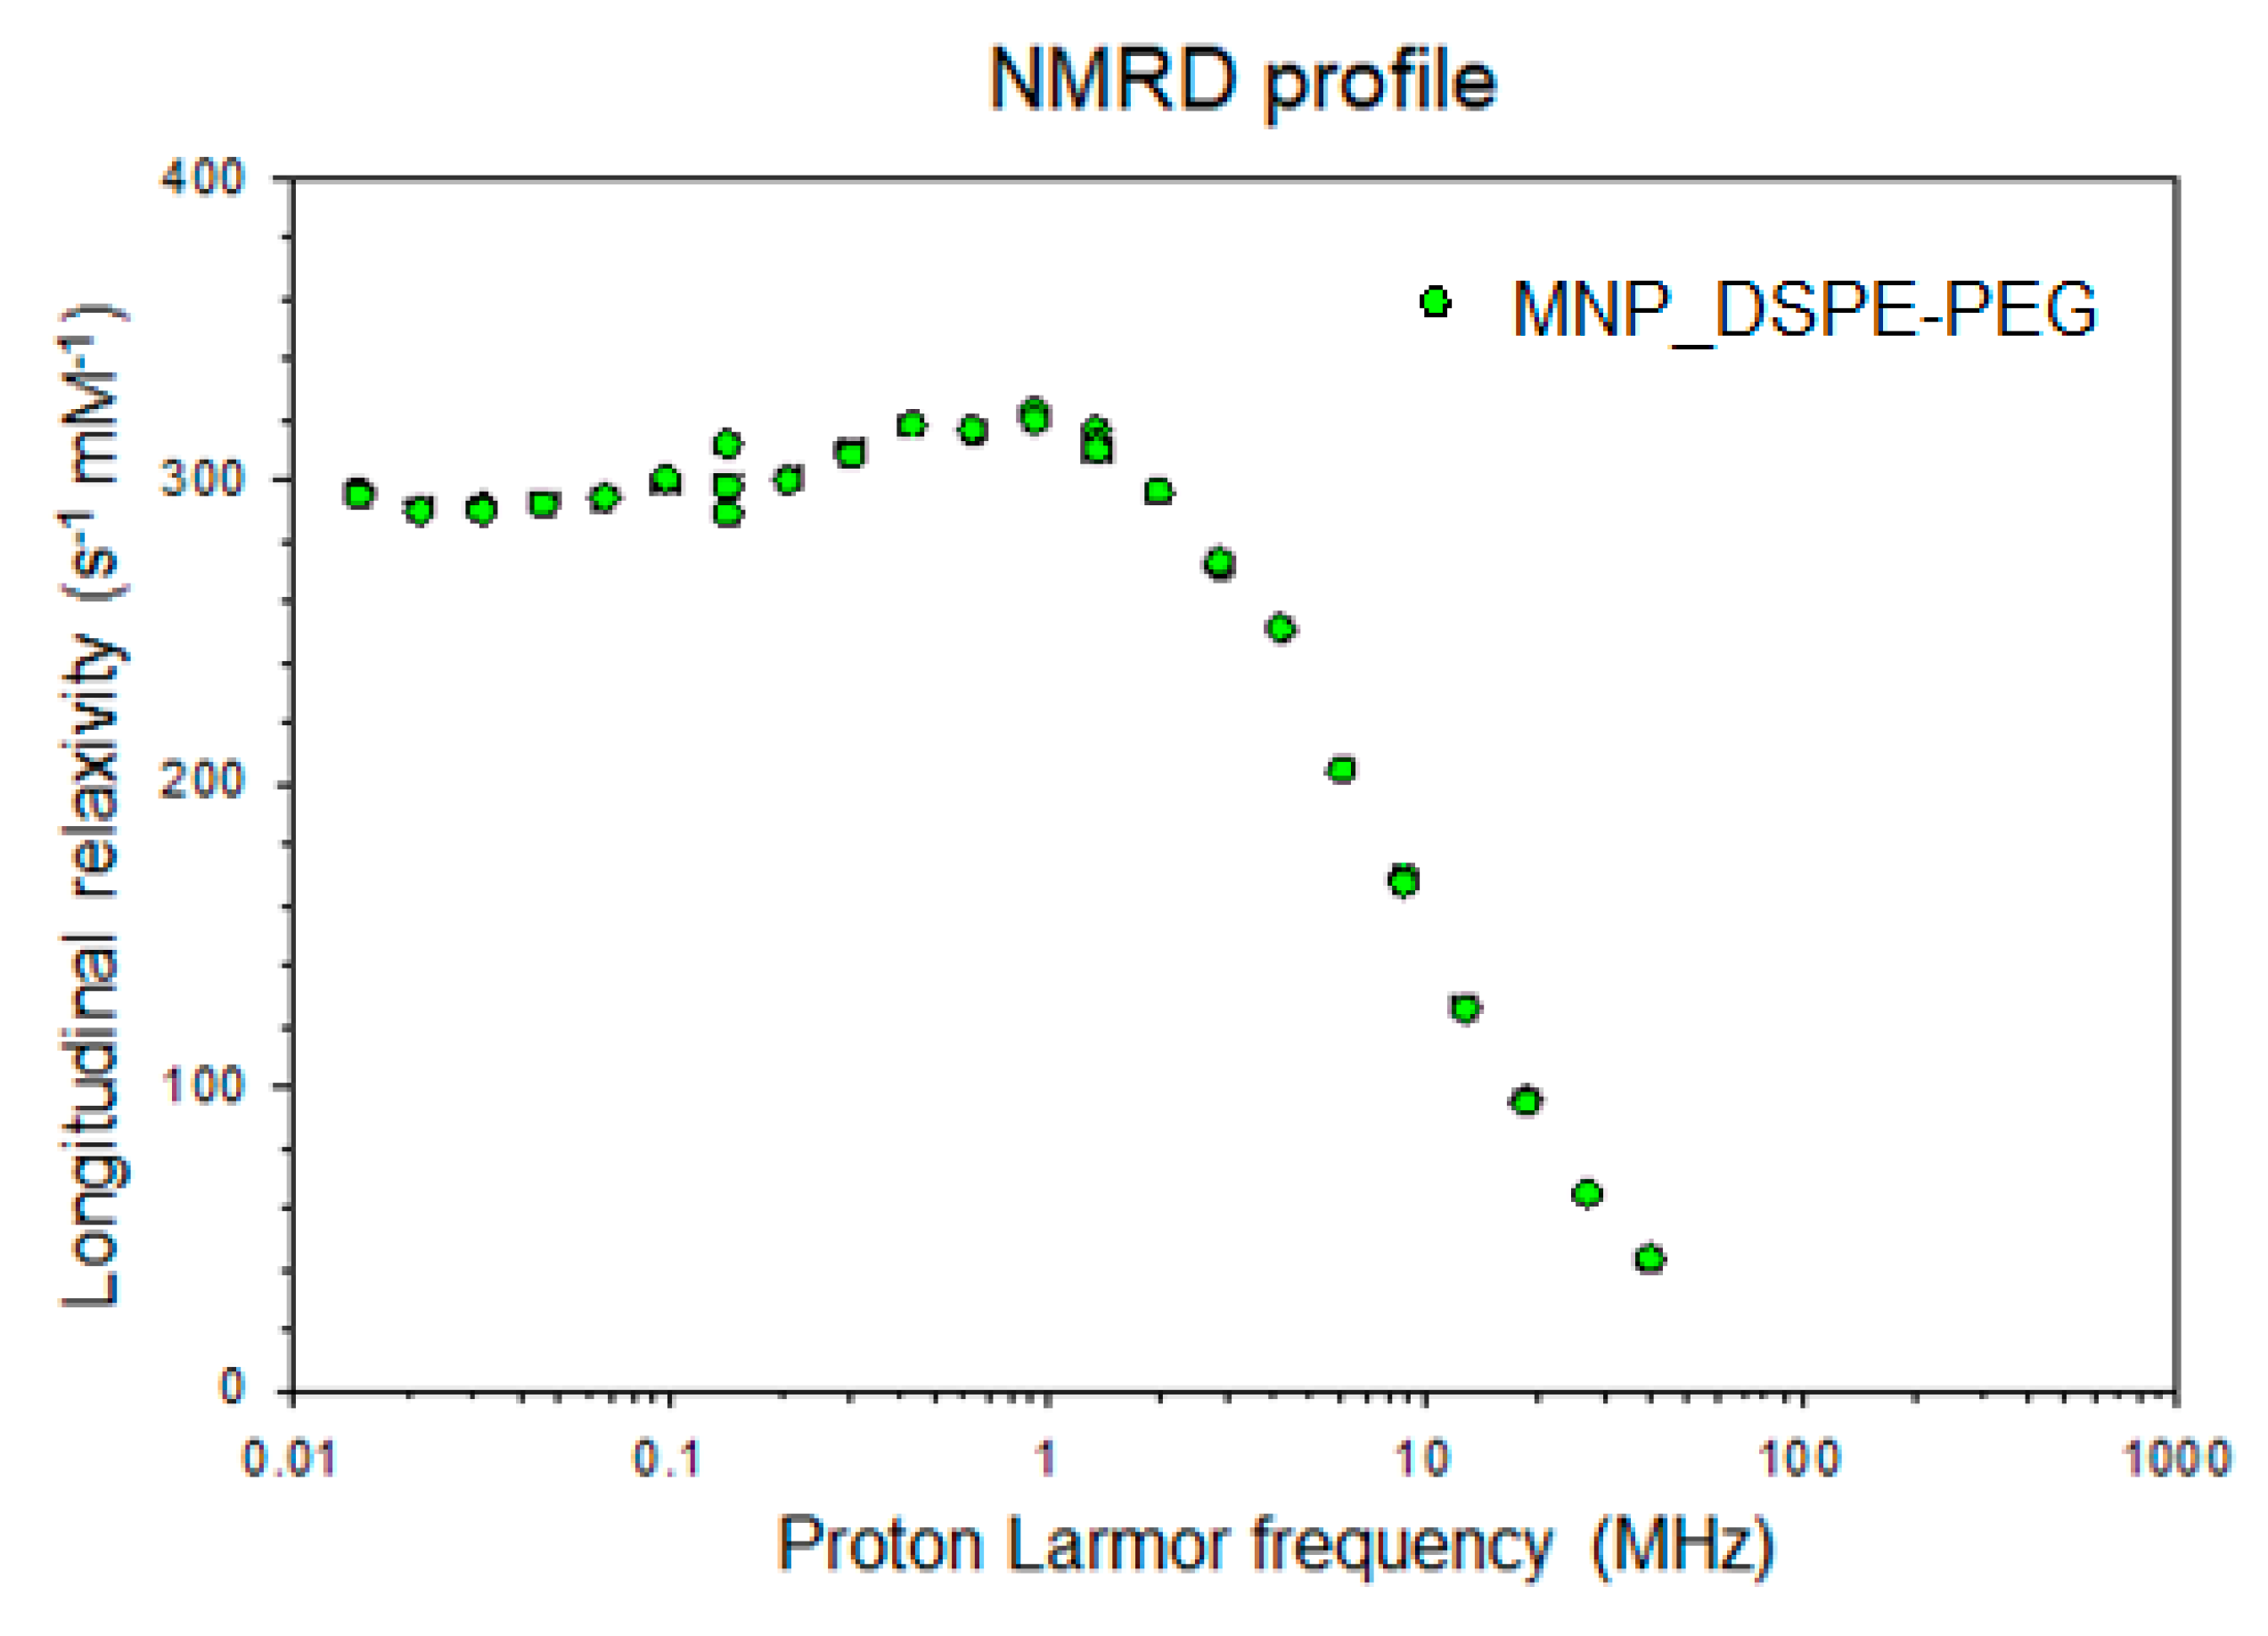

2.6. Nuclear Magnetic Relaxation Dispersion (NMRD) Profile and Relaxivity Measurements

| Parameters | r1 (s−1 mM−1) | r2 (s−1 mM−1) | r2/r1 (s−1 mM−1) |

|---|---|---|---|

| 20 MHz | 15.39 | 151.23 | 9.83 |

| 60 MHz | 3.85 | 183.48 | 47.66 |